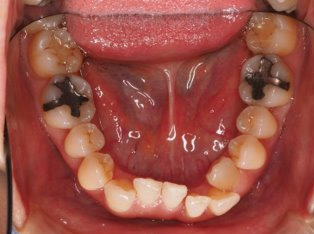

乱ぐい歯、でこぼこがとても酷い状態になります。歯が前後的に重なってしまっている、八重歯になっているなどがこのジャンルに入ります。

顎の大きさと歯の大きさのギャップが大きく、時には歯を抜かないと矯正治療ができない場合もあります。当院では治療期間が長くなるが抜かない治療方針など、一つの治療プランだけでなく、さまざまな可能性の治療方針を説明させて頂くよう心掛けております。こういった考え方はインフォームド・チョイスと言われ近年大切にされている考え方と言われております。

治療前

治療終了前